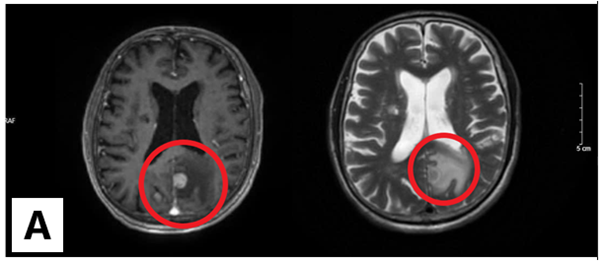

Chụp cộng hưởng từ sọ não: Nhu mô não vùng trên lều tiểu não có các nốt tổn thương nhu mô não dưới vỏ thuỳ trán trái, thùy đỉnh hai bên và thùy chẩm phải, đường kính ổ tổn thương lớn nhất 12mm, ngấm thuốc mạnh sau tiêm, có phù não rộng xung quanh.

Hình 2: Hình ảnh cộng hưởng từ sọ não: Các nốt tổn thương nhu mô não ngấm thuốc mạnh sau tiêm, có phù não rộng xung quanh (vòng tròn màu đỏ)(B: Thùy chẩm, A,C: Thùy đỉnh)

Hình ảnh chụp cộng hưởng từ sọ não sau 3 chu kỳ điều trị hóa chất:

Trước điều trị

Sau điều trị

Hình 4: Hình ảnh chụp cộng hưởng từ sọ não trước và sau điều trị

Nhận xét: Trước điều trị hóa chất xuất hiện hình ảnh nhu mô não có các nốt tổn thương nhu mô não hai bên ngấm thuốc mạnh sau tiêm, có phù não rộng xung quanh, tuy nhiên sau điều trị hóa chất 3 chu kỳ, không còn thấy hình ảnh tổn thương thứ phát tại não.